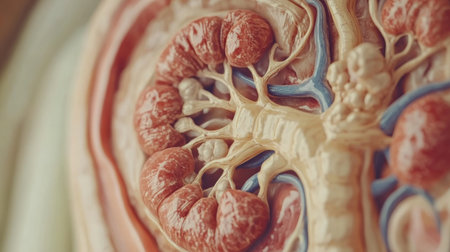

A close-up of the human kidney with visible structures such as nephrons and blood vessels, set on a neutral background with a focus on details

Anatomical image of the human kidney in cross section. disorders of kidney physiology,